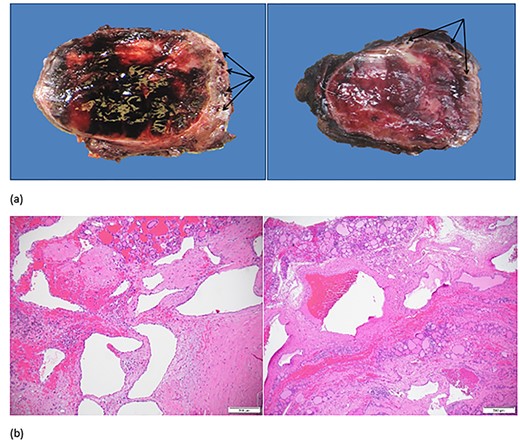

Pathologic examination of the right thyroid lobe revealed a dominant adenomatous nodule with Hürthle cell and degenerative changes. A proliferation of large arterial and venous structures was seen predominantly at the periphery of the nodule and in the adjacent soft tissue (Fig. 3). The findings were consistent with an AVM. Consultation with an institutional expert on AVM syndromes resulted in recommendation for vascular imaging of the head and neck to evaluate for other possible associated AVMs. Follow-up imaging revealed no additional head or neck AVMs.

(a) Right thyroid gland with enlarged vessels (arrows) and hemorrhagic parenchyma on gross examination. (b) Large arterial and venous structures with background adenomatous and degenerative changes in the thyroid on microscopic examination.